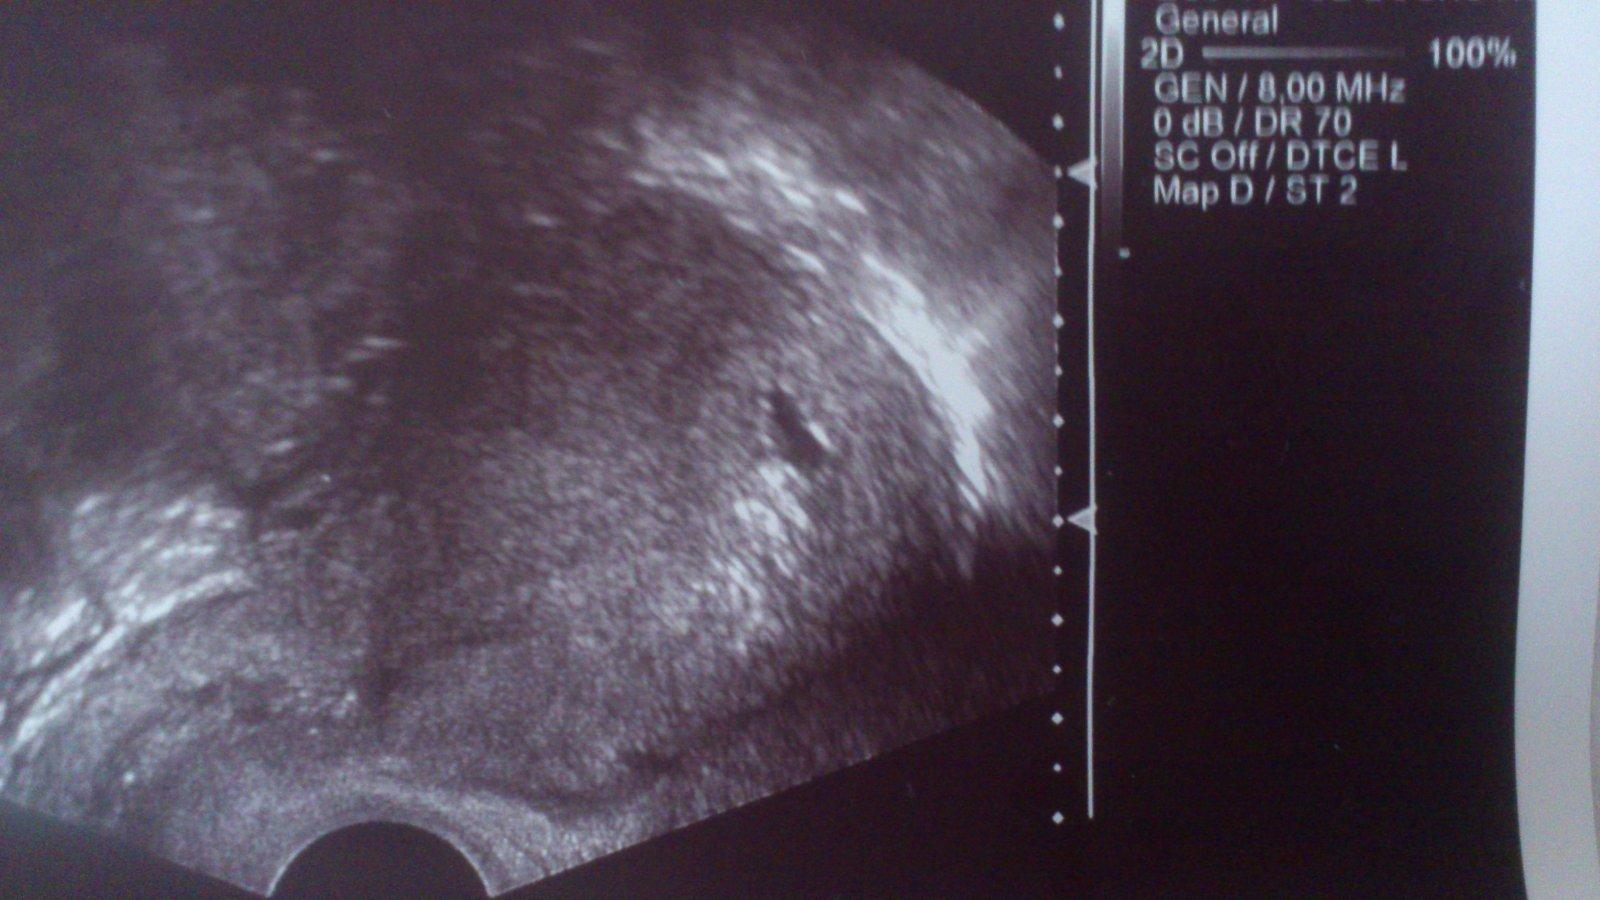

Ahoj holky, som po prvnim UTZ. Zatim mame len gest.vacek odpovidajici 5.-6.tt. Dle ms som 6+0tt, ale bezpecne viem, ze ovu bola o 4-5 dni neskor, takze som si upravila zacatek ms o tie 4 dni, takze realne som tak 5+3tt. Zvysene lieky, odoslali ma na hematologiu koli protilatkam ana, anca a ovarialnym. Hrozia mi injekcie. Zatial sa nemame upinat na tehu, je to hodne nejiste koli mojej imunite. Dobra sprava je to, ze to nie je mimodelozni. 🙂 Zaroven posledny test 25DPO.